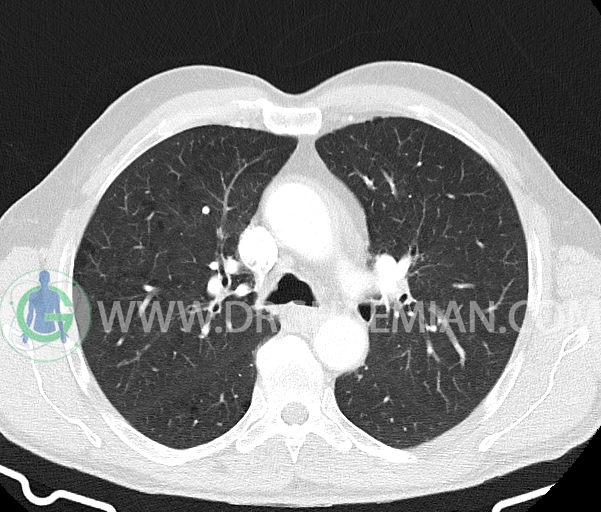

تراشه و برونش های اصلی نرمال اند.

توده ریوی، پلورال افیوژن، جابجایی محتویات مدیاستن، کلسیفیکاسیون، کیست، فیبروز ریوی و Collection مشهود نیست.

–چند لنف نود در مدیاستن میانی و قدامی به حداکثر SAD=8mm در پره کارینا (بدون اهمیت بالینی)

–دو لنف نود در هیلوم ریه راست به حداکثر SAD=8mm